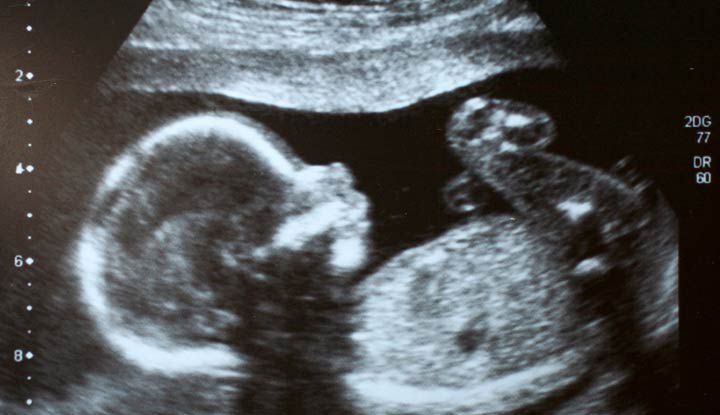

Seeing an ultrasound, hearing a heartbeat, those moments can make things “click” in a way nothing else does.